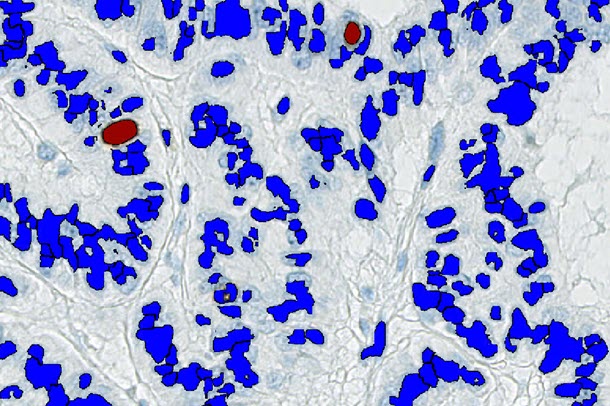

To train and test a machine learning system

The trained algorithm performs very well in counting negative (= red) and positive (= green) tumour cells.